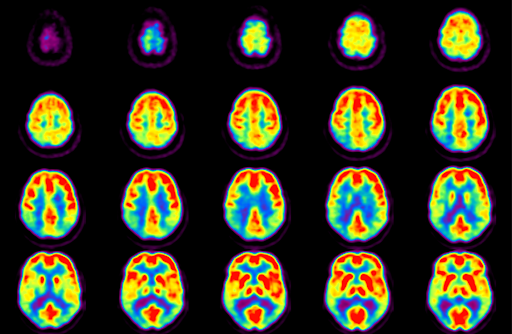

PET scan stands for ‘Positron Emission Topography’. It is helpful in studying the activity of brain. The radioactive tracers attached to glucose enter the brain through bloodstream. The rate of utilization of radioactive glucose indicates the different areas of brain activity. Indications of PET scan are: - Detection of tumors - Detection of metastasis - Diagnosis of dementias - Epilepsy surgery Reference: https://www.healthline.com/health/brain-pet-scan#procedure Image via: http://bachlab.pitt.edu/facilities/pet-imaging